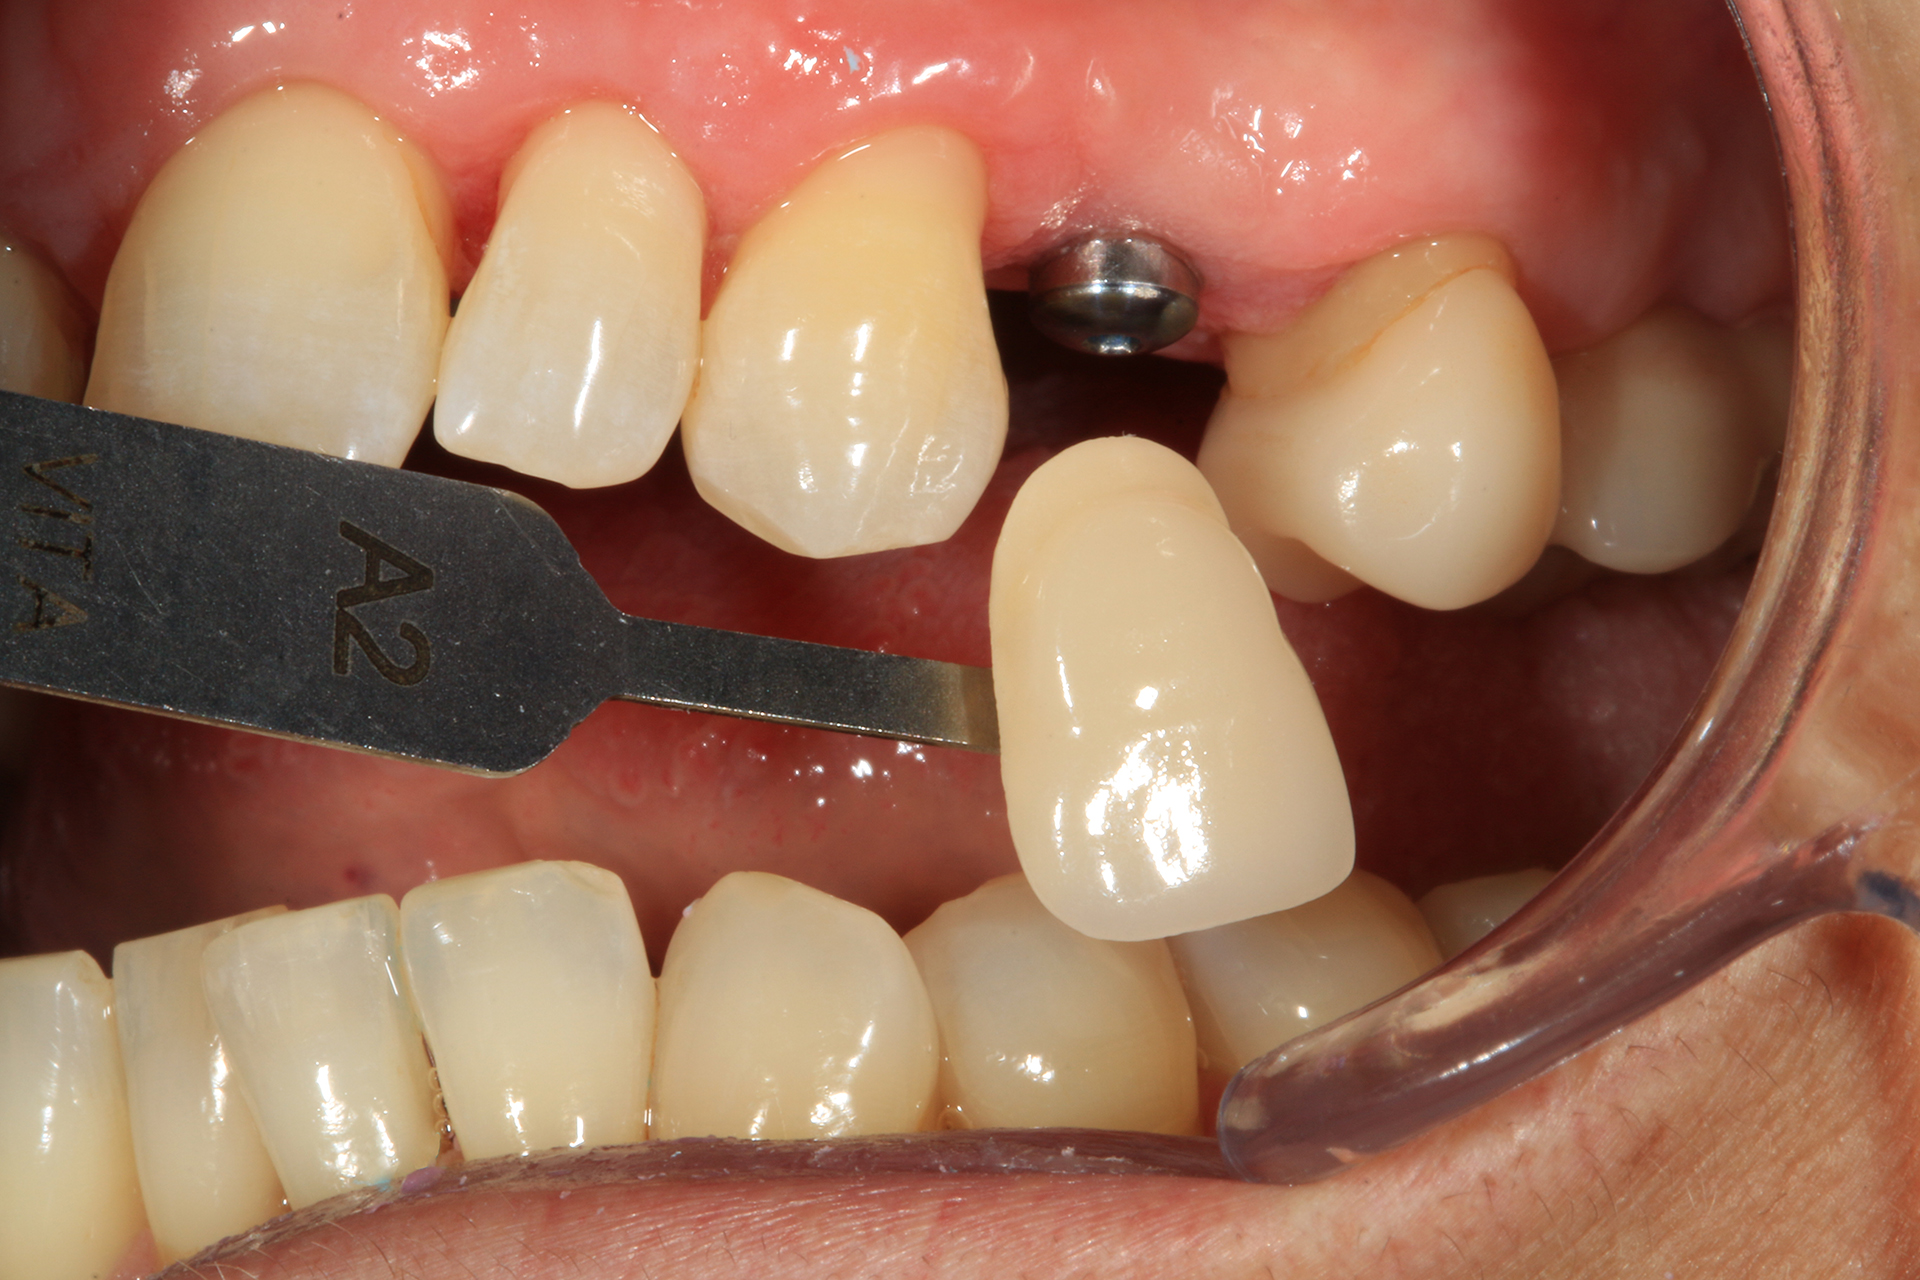

Grazie a dima e drivers, la chirurgia guidata consente una fresatura biologicamente incrementale come con un protocollo convenzionale; l’osso autologo raccolto durante la fresatura può essere utilizzato come particolato da innesto al bisogno. I dati clinici e demografici raccolti includono età, sesso, storia clinica e terapie farmacologiche in atto. I dati correlati agli impianti includono, invece, localizzazione anatomica, diametro, lunghezza, torque di inserzione, tipo di protesi, e parametri ossei rilevati alla diagnosi (Figure 2-3). Nel corso del follow-up sono stati registrati la sopravvivenza implantare protesica e il livello di osso marginale. I dati sono stati registrati da un esaminatore indipendente.

Il 20% degli impianti è stato posizionato nella mandibola (per lo più in posizione 47) e il restante 80% nel mascellare superiore (il 20% in posizione 16 e il 20% in posizione 25). Gli impianti posizionati nel mascellare superiore hanno trovato un osso tipo IV, mentre gli impianti posizionati nella mandibola hanno trovato un osso tipo III. Gli impianti utilizzati hanno un diametro compreso tra 4.0 e 4,5 mm (il 66.7% sono da 4.0 mm) e una lunghezza compresa tra 4.5 mm e 7.5 mm (il 53.3% sono lunghi 7.5 mm). Nell’86.7% dei casi non è stato eseguito alcun procedimento chirurgico aggiuntivo; in un caso, due impianti hanno previsto in rialzo di seno transcrestale con PRGF-Endoret e osso autologo. Nel 93.3% dei casi la protesizzazione ha previsto ponti avvitati a più elementi; un impianto è stato protesizzato mediante elemento singolo avvitato con componente transepiteliale. Il follow-up medio è stato di 12.4 ± 1.05 mesi dal carico. Il 100% degli impianti è sopravvissuto, senza complicanze né chirurgiche né protesiche. La perdita di osso media a 12 mesi è stata mesialmente di 0.15 ± 0.74 mm e distalmente di 0.13 ± 0.85 mm. La Figura 4 mostra l’osso perso su un singolo impianto e le Figure 5-14 illustrano un caso clinico rappresentativo.